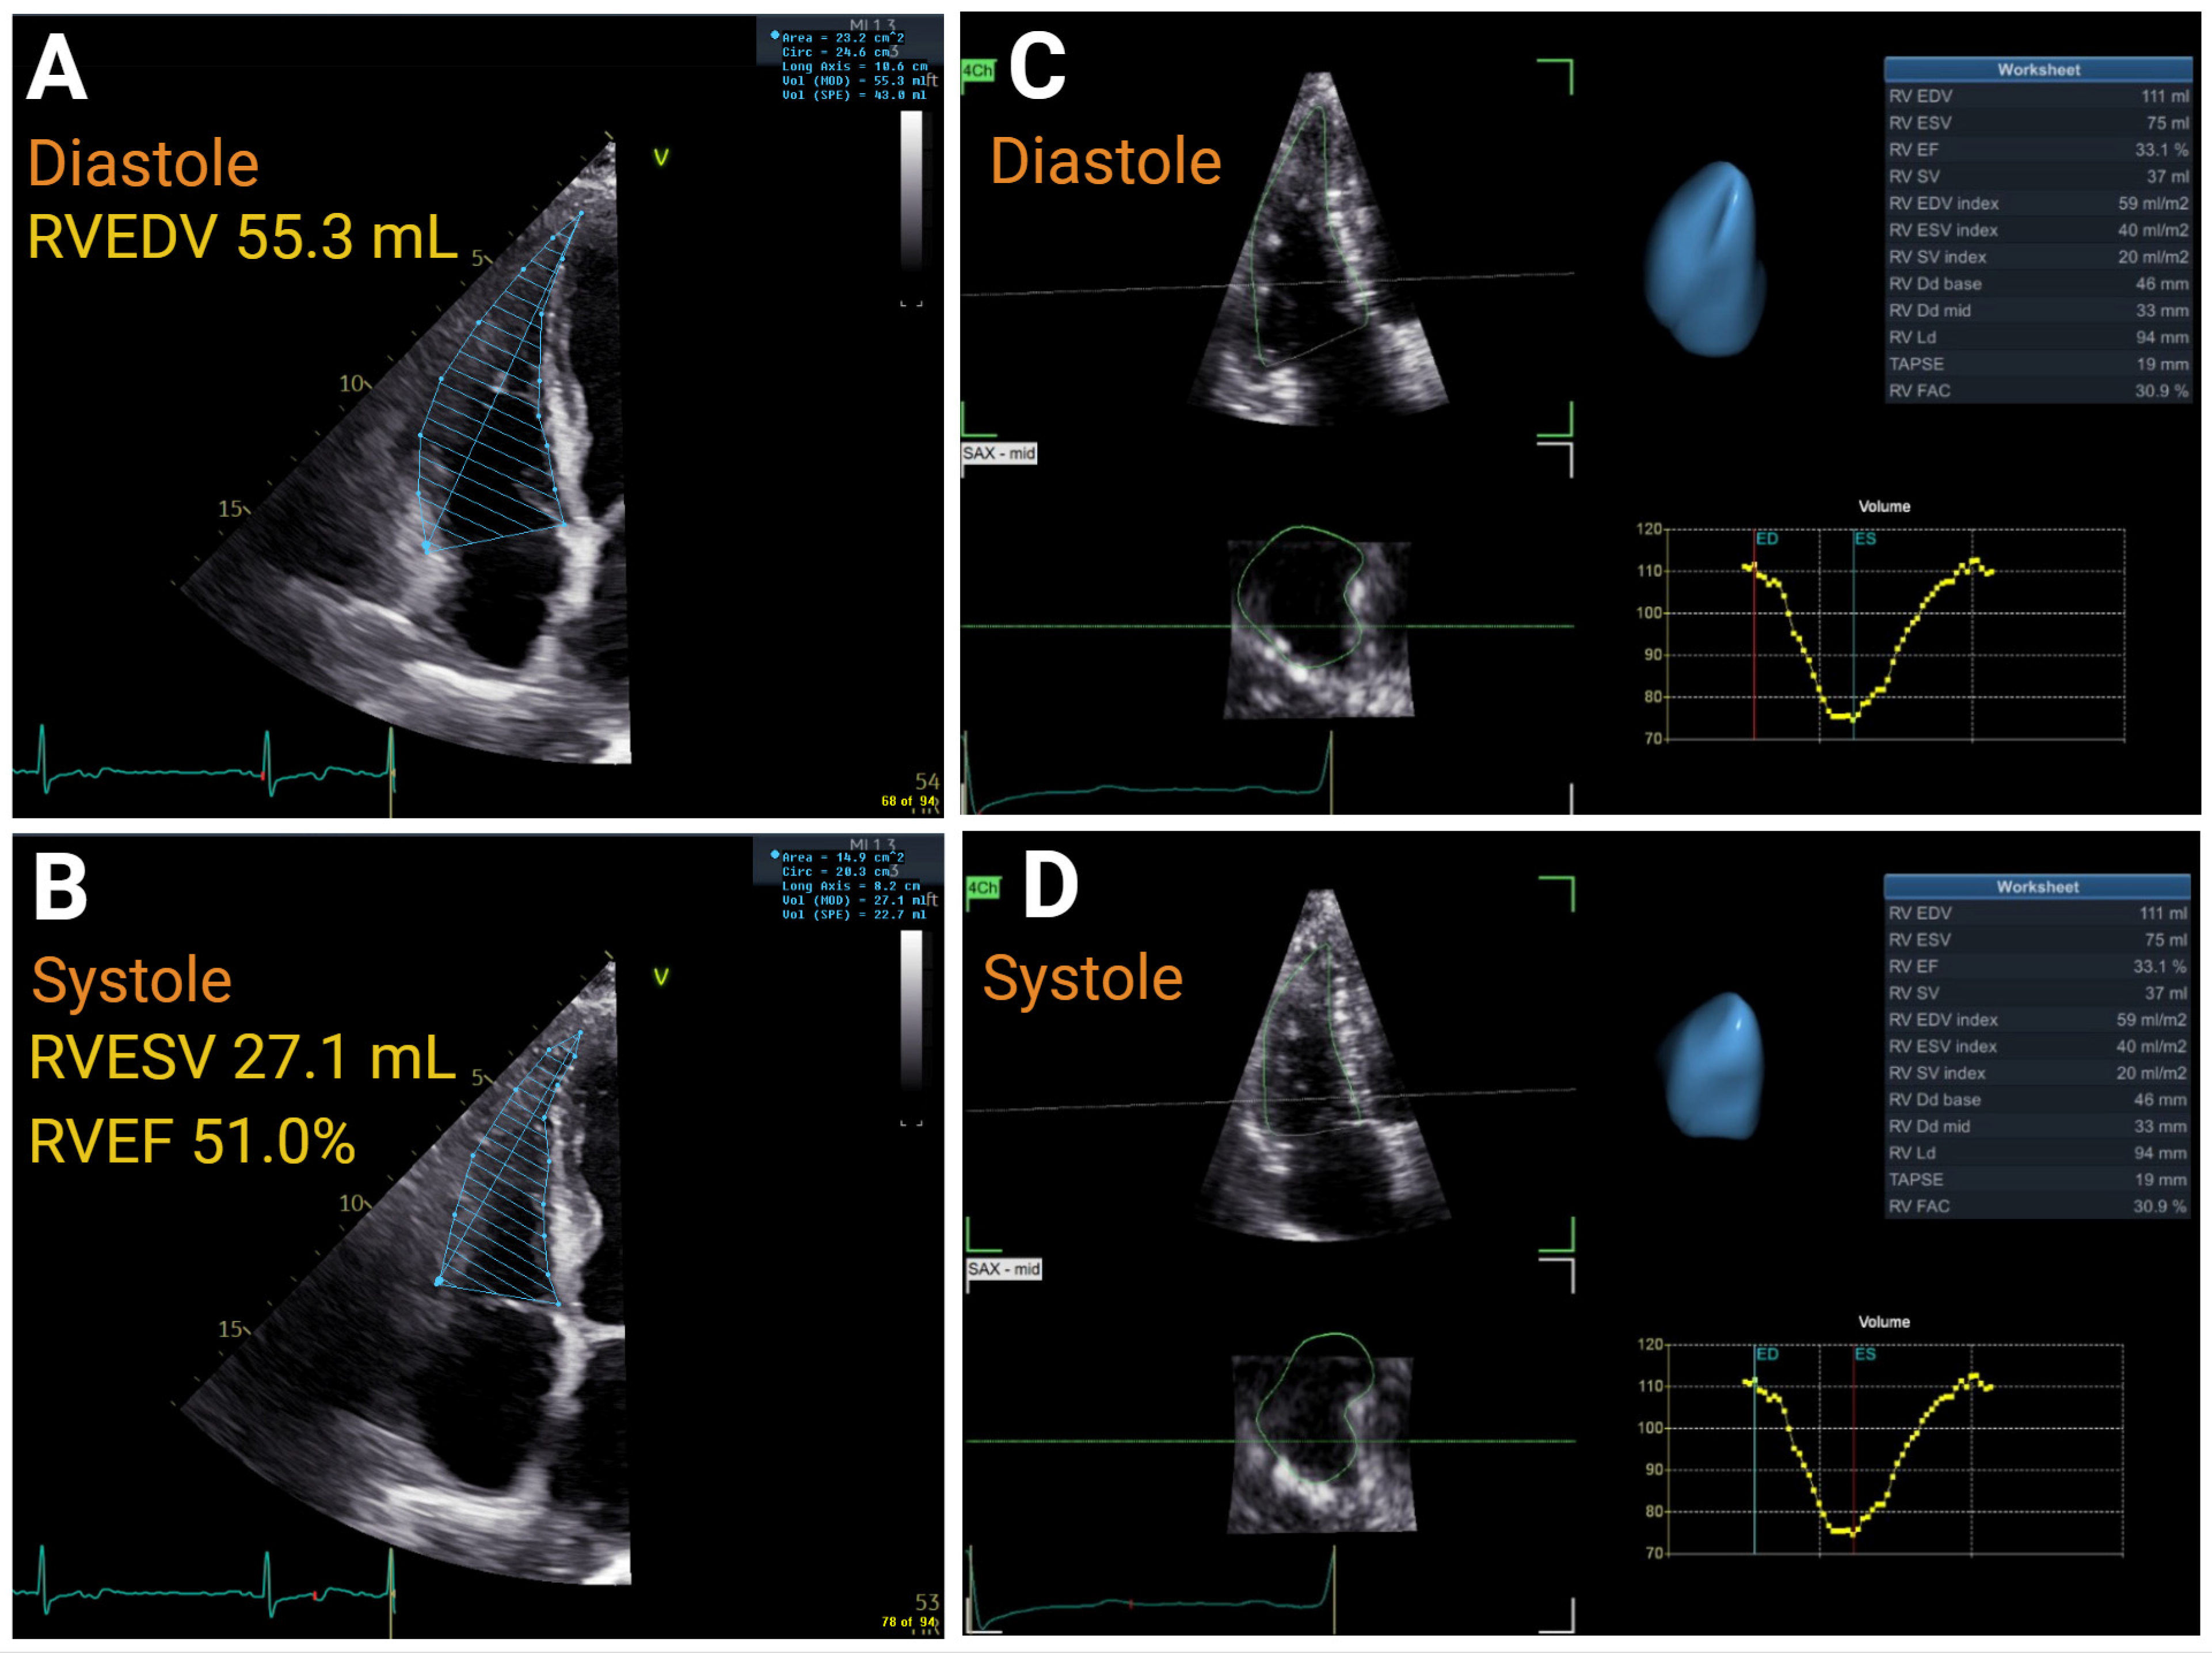

| Right Ventricular Systolic Function | ||||||

| TAPSE, cm | >1.7 | ≤1.7 to ≥1.3 | ≤1.3 to >1.0 | ≤1.0 | r = 0.45 to 0.62 | AUC = 0.74 |

| S′, cm/s | >9.5 | ≤9.5 to ≥7.2 | ≤7.2 to >5.0 | ≤5 | r = 0.36 to 0.52 | |

| FAC, % | >35 | ≤35 to >29 | ≤29 to >22 | ≤22 | r = 0.55 to 0.77 | AUC = 0.83 |

| RV FWS, % | >20 | ≤20 to <15 | <15 to ≥11 | <11 | r = 0.69 to 0.92 | |

| 3D RVEF, % | >45 | ≤45 to <39 | ≤39 to ≤32 | <32 | r = 0.56 to 0.95 | |